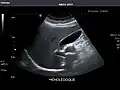

Standard measurement of the abdominal aorta[4]

It can be used on the abdominal aorta to detect or exclude abdominal aortic aneurysm. For this purpose, the standard aortic measurement for abdominal aortic aneurysm is between the outer margins of the aortic wall.[4]

Aorta: Visualized portions normal in caliber, 16 x 15 mm.